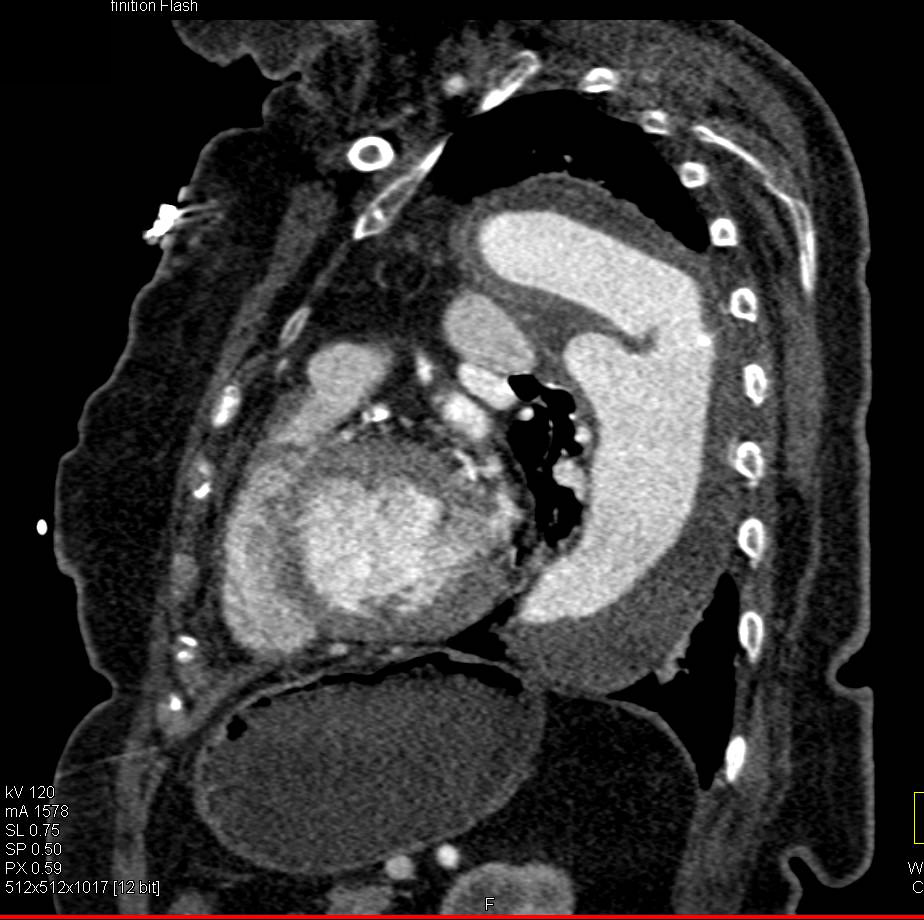

Tracheal Stenosis with Tracheostomy Tube in Place